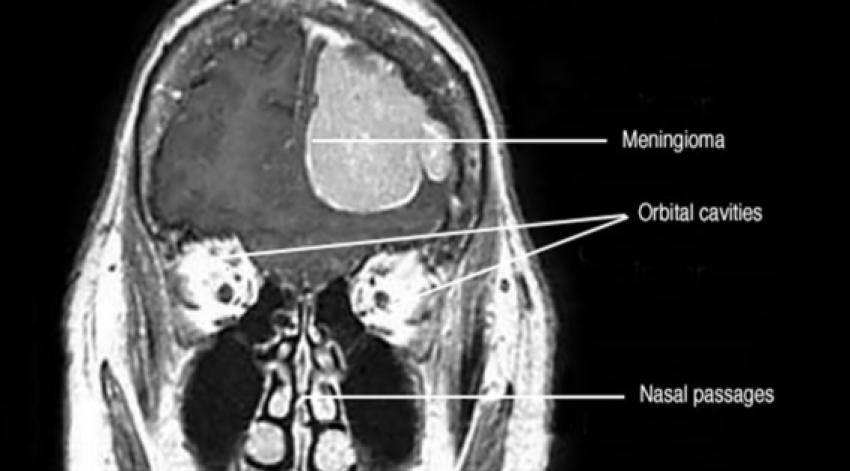

Generally, meningiomas are indolent and can be overlooked for quite a long time. On the other hand, if they get to a certain size or if their location is in a sensitive part of the brain, symptoms like continuous headache, impairment of vision, memory loss, or difficulty with motor function can be observed. Early detection by MRI and CT is very important for the diagnosis to be correct. In Kolkata, several credible medical centres are opening, providing not only the latest imaging equipment but also the training of neurologists for the diagnosis and therapy of these tumors.